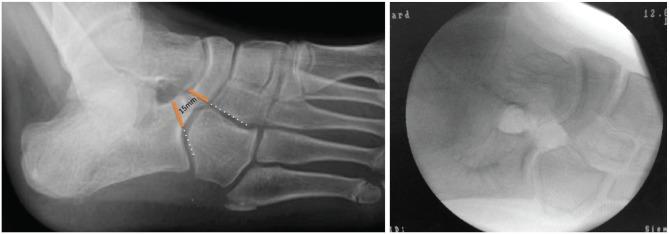

A tarsal coalition is an abnormal connection between two or more tarsal bones caused by failure of mesenchymal segmentation.The two most common tarsal coalitions are calcaneonavicular coalition (CNC) and talocalcaneal coalition (TCC). Both CNC and TCC can be associated with significant foot and ankle pain and impaired quality of life; there may also be concomitant foot and ankle deformity.Initial, non-operative management for symptomatic tarsal coalition commonly fails, leaving surgical intervention as the only recourse.The focus of this article is to critically describe the variety of methods used to surgically manage CNC and TCC. In review of the pertinent literature we highlight the ongoing treatment controversies in this field and discuss new innovations.The evidence-based algorithmic approach used by the authors in the management of tarsal coalitions is illustrated alongside some clinical pearls that should help surgeons treating this common, and at times complex, condition. Cite this article: 2020;5:80-89. DOI: 10.1302/2058-5241.5.180106.

跗骨联合是由于间充质节段化失败导致两块或多块跗骨之间的异常连接。最常见的两种跗骨联合是跟舟联合(CNC)和距跟联合(TCC)。CNC和TCC都可能伴有严重的足踝疼痛和生活质量受损;也可能伴有足踝畸形。对于有症状的跗骨联合,最初的非手术治疗通常无效,手术干预成为唯一的选择。本文的重点是批判性地描述用于手术治疗CNC和TCC的各种方法。在回顾相关文献时,我们强调了该领域持续存在的治疗争议并讨论了新的创新方法。作者在跗骨联合管理中使用的循证算法方法与一些临床要点一起展示,这些要点应有助于外科医生治疗这种常见且有时复杂的病症。引用本文:2020;5:80 - 89。DOI: 10.1302/2058 - 5241.5.180106。